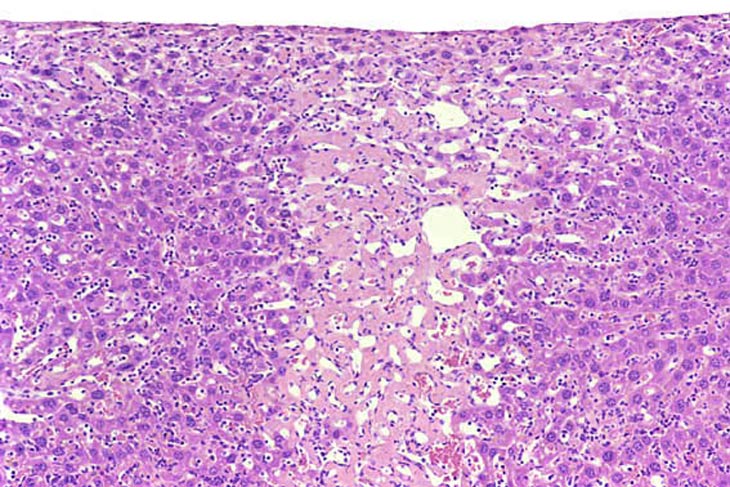

Focal coagulation necrosis.

Another example of focal necrosis.